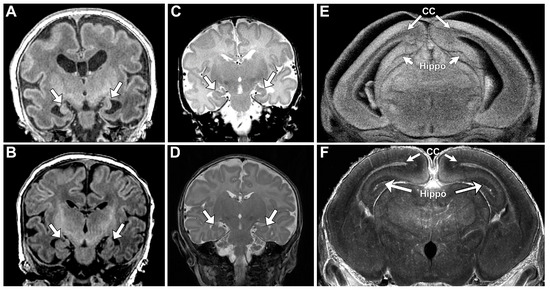

Lack of oral feeding before neonatal hospital discharge was associated with multiple morphological abnormalities of the components of the BDS including cerebellar hemispheres and vermis, hippocampus, bilateral olfactory bulbs and olfactory sulci, corpus callosum, increased supratentorial extra-axial fluid, as well as total increased BDS (Table 7). Hospital length of stay was associated with dysplasia of the cerebellar hemispheres and vermis, hippocampus, choroid plexus, brainstem, increased supratentorial axial fluid, and BDS (Table 7). A diagnosis of dysphasia was associated with dysplasia of the brain stem ((p = 0.001) Table 7). Gastrointestinal dysmotility, aspiration, gastroesophageal reflux, malrotation, and vocal cord paralysis demonstrated no significant associations with brain dysplasia (Table 7). Figure 2 panels A–D show some of the variations in hippocampal anatomy seen in the human population compared against that seen in the mouse in panels E and F. Figure 3 demonstrates olfactory bulb abnormalities in human infant CHD vs. control (A/C) and the mouse model (B/D). Figure 4 demonstrates cerebellar abnormalities in the human infant CHD vs. controls (A,B) and the mouse model (E,F).

An important component of our paralimbic-related subcortical BDS scoring system is the hippocampus. We found a consistent pattern of dysmaturation in the hippocampus, including severe forms of hippocampal aplasia or dysplasia in both mice and human subjects. Research has indicated that reductions in hippocampal volume has functional correlates in adolescents and adults, resulting in an increased rate of neurodevelopmental impairment [65,66]. Fontes et al. found that hippocampal shape and volumetric abnormalities found within CHD subjects can be predictive of impaired executive function. It is possible that the hippocampus is particularly vulnerable to early injury in CHD individuals as it is a brain region particularly susceptible to injury related to hypoxemia or hemodynamic instability. Latal et al. found that reductions in hippocampal volume correlated with reductions in total IQ, working memory, and verbal comprehension. Lastly, one study looking at maternal stress found that reductions in hippocampal volumes are present in utero, consistent with previous volumetric findings of CHD [67]. Wu et al. concluded that universal screening looking at maternal stress is important, as early identification of hippocampal abnormalities is imperative.